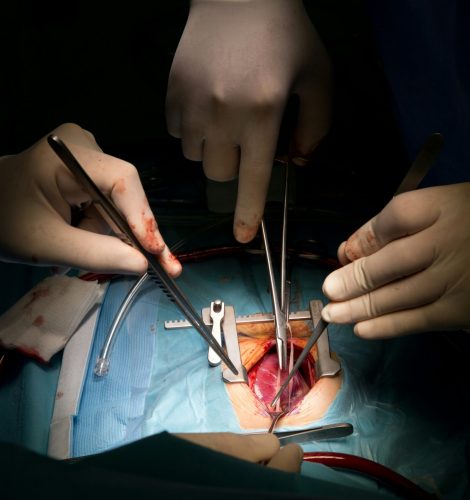

- Advanced medical technology: Equipped with cutting-edge diagnostic systems, imaging tools, and surgical technology for accurate and effective treatment.

SPECIALIZED TREATMENTS

DEPARTMENT OF

SURGERY